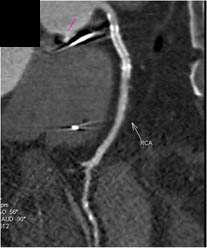

Diseased LAD